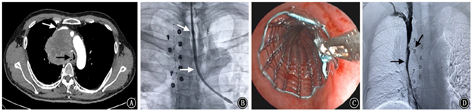

若良、恶性肿瘤同时压迫了上腔静脉和气道,通常会出现明显呼吸困难、头面部及上肢肿胀、胸壁静脉曲张及中枢神经等症状,严重时可导致猝死,而此类患者多属晚期肿瘤不适合行外科手术切除肿瘤,内科药物治疗效果欠佳。对于此类患者,可以联合血管介入和内镜介入,同台置入气道支架和上腔静脉支架,缓解气道阻塞和上腔静脉阻塞。若还未明确肿瘤性质,同时还可以进行SAE栓塞肿瘤供血血管,再行气道内活检,联合操作可缩短患者诊治周期,提高安全性。但目前对于双支架的临床报道多为个案或病例系列报道,尚缺乏随机对照研究,也缺乏评估血管或气道狭窄患者的动力学的指标来评估有效性,还需要进一步研究。具体流程见图6。病例4:男性患者,64岁;因"憋喘伴颜面水肿3 d"入院,既往确诊为肺鳞癌;胸部CT提示肿块明显压迫气道及上腔静脉。见图7。